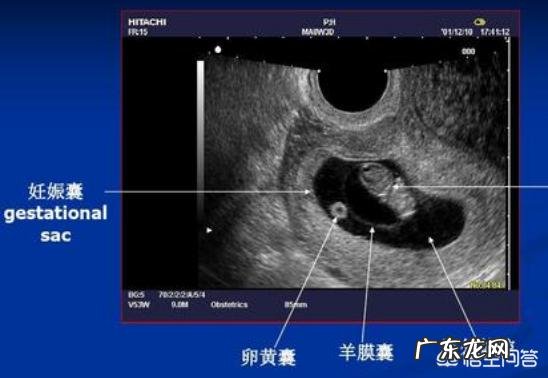

2、B超检查:到了怀孕6-8周或怀孕12周 , 一般会到医院做个超声波检查 , 可以确诊是否怀孕 , 也能诊断出是否正常怀孕 , 判断是宫内妊娠还是宫外妊娠、胚胎是否存活、是否出现胎心胎芽 , 通过这些来确定有无先兆流产和胎停育征兆 , 也就是间接的判断胎儿的发育情况 , 是否存在胎儿发育不良 。